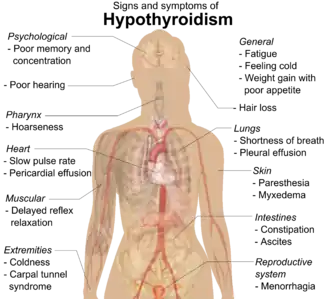

Signs and symptoms

Systemic manifestations of hypothyroidism

Signs

As lymphocytic infiltration progresses, patients may exhibit signs of hypothyroidism in multiple bodily systems, including, but not limited to, a larger goiter, weight gain, cold intolerance, fatigue, myxedema, constipation, menstrual disturbances, pale or dry skin, and dry, brittle hair, depression, and ataxia.[14][10] Extended thyroid hormone deficiency may lead to muscle fibre changes, resulting in muscle weakness, muscle pain, stiffness, and rarely, pseudohypertrophy.[15] Patients with goiters who have had autoimmune thyroiditis for many years might see their goiter shrink in the later stages of the disease due to destruction of the thyroid.[1] Graves disease may occur before or after the development of autoimmune thyroiditis.[16]

While rare, more serious complications of the hypothyroidism resulting from autoimmune thyroiditis are pericardial effusion, pleural effusion, both of which require further medical attention, and myxedema coma, which is an endocrine emergency.[10]

Many symptoms are attributed to the development of Hashimoto's thyroiditis. Symptoms can include: fatigue, weight gain, pale or puffy face, feeling cold, joint and muscle pain, constipation, dry and thinning hair, heavy menstrual flow or irregular periods, depression, a slowed heart rate, problems getting pregnant, miscarriages,[17] and myopathy.[15] Some patients in the early stage of the disease may experience symptoms of hyperthyroidism due to the release of thyroid hormones from intermittent thyroid destruction[10][18] (also called "destructive thyrotoxicosis").[5] In non-medical settings, the term "flare" is used to refer to a sudden exacerbation of symptoms, whether hyper or hypo.[19]

While most symptoms are attributed to hypothyroidism, similar symptoms are observed in Hashimoto's patients with normal thyroid hormone levels.[20][21][13] According to one study, these symptoms may include lower quality of life, and issues of the "digestive system (abdominal distension, constipation and diarrhea), endocrine system (chilliness, gain weight and facial edema), neuropsychiatric system (forgetfulness, anxiety, depressed, fatigue, insomnia, irritability, and indifferent [sic]) and mucocutaneous system (dry skin, pruritus, and hair loss)."[22]